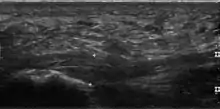

Thickened plantar fascia in ultrasound

Plantar fasciitis is usually diagnosed by a health care provider after consideration of a person's presenting history, risk factors, and clinical examination.[4][17][18] Palpation along the inner aspect of the heel bone on the sole may elicit tenderness during the physical examination.[4][11] The foot may have limited dorsiflexion due to excessive tightness of the calf muscles or the Achilles tendon.[7] Dorsiflexion of the foot may elicit the pain due to stretching of the plantar fascia with this motion.[4][12] Diagnostic imaging studies are not usually needed to diagnose plantar fasciitis.[7] Occasionally, a physician may decide imaging studies (such as X-rays, diagnostic ultrasound, or MRI) are warranted to rule out serious causes of foot pain.

The plantar fascia has three fascicles-the central fascicle being the thickest at 4 mm, the lateral fascicle at 2 mm, and the medial less than a millimeter thick.[19] In theory, plantar fasciitis becomes more likely as the plantar fascia's thickness at the calcaneal insertion increases. A thickness of more than 4.5 mm ultrasound and 4 mm on MRI are useful for diagnosis.[20] Other imaging findings, such as thickening of the plantar aponeurosis, are nonspecific and have limited usefulness in diagnosing plantar fasciitis.[13]